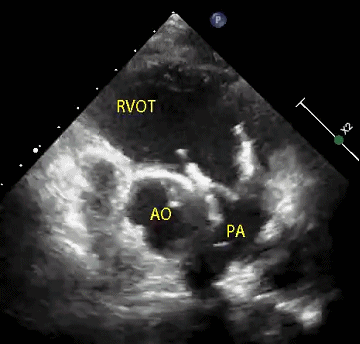

患者男性,11岁,因先天性肺动脉闭锁行带瓣补片右室流出道重建术后11年,近期症状加重,心脏超声提示肺动脉瓣重度返流。术前行详细影像学重建与评估及多学科讨论手术策略。影像学重建显示患者肺动脉较短,截面呈椭圆形,腰部径宽16-32mm,形态测算介入瓣植入后直径22mm。手术经胸小切口入路,通过食道超声定位,经右室流出道穿刺植入22号Salus介入瓣。由于此前应用带瓣补片重建的主肺动脉质地较硬,主肺动脉截面形状较扁呈椭圆而非正圆形,介入瓣释放后支架四周难以与主肺动脉内壁完全贴合,食道超声提示主肺动脉右侧存在少量瓣周漏。继而行环缩部分主肺动脉。再次行经食道超声及肺动脉造影显示介入瓣植入位置理想,无瓣周漏及中央返流。

病例1 术后超声